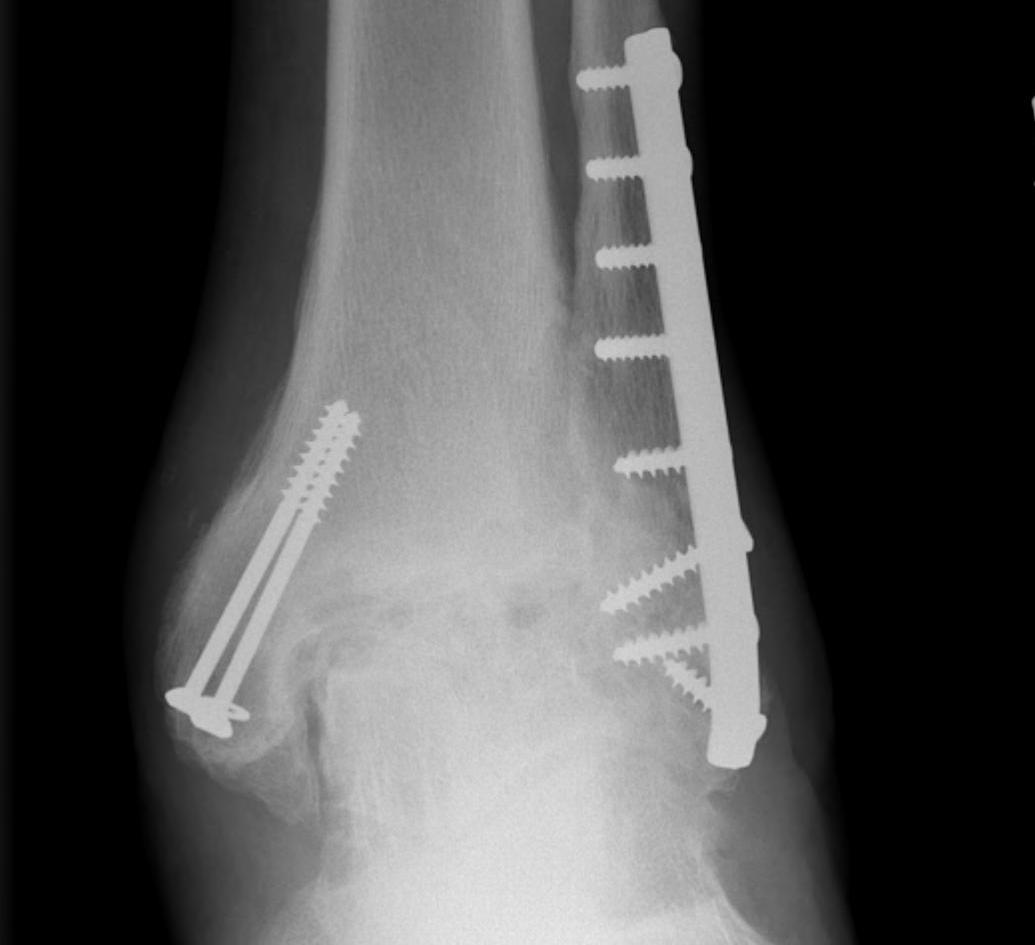

Operative Management

trimallTrimallTrimallTrimall

ankeankleankleankle